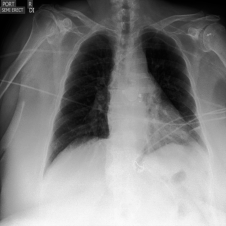

Deep predictive models often make use of spurious correlations between the label and the covariates that differ between training and test distributions. In many classification tasks, spurious correlations are induced by a changing relationship between the label and some nuisance variables correlated with the covariates. For example, in classifying animals in natural images, the background, which is the nuisance, can predict the type of animal. This nuisance-label relationship does not always hold. We formalize a family of distributions that only differ in the nuisance-label relationship and introduce a distribution where this relationship is broken called the nuisance-randomized distribution. We introduce a set of predictive models built from the nuisance-randomized distribution with representations, that when conditioned on, do not correlate the label and the nuisance. For models in this set, we lower bound the performance for any member of the family with the mutual information between the representation and the label under the nuisance-randomized distribution. To build predictive models that maximize the performance lower bound, we develop Nuisance-Randomized Distillation (NURD). We evaluate NURD on a synthetic example, colored-MNIST, and classifying chest X-rays. When using non-lung patches as the nuisance in classifying chest X-rays, NURD produces models that predict pneumonia under strong spurious correlations.